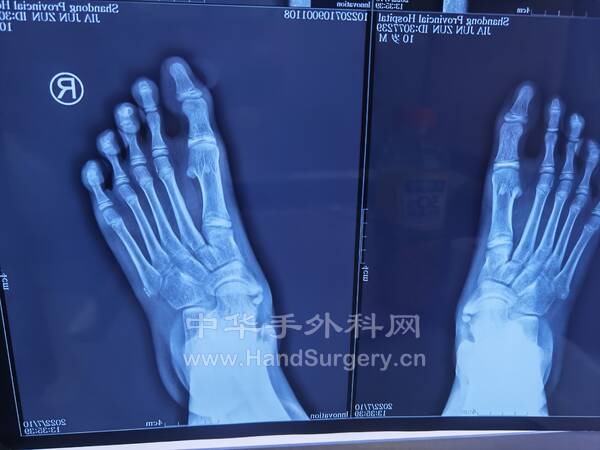

1.男,16岁双足马蹄足,儿麻后遗症,偏瘫,可行手术治疗(图1-5)

6.男,5岁,双足踇外翻(目前见过的最小拇外翻患者)(图6)

IMG_20220717_145337.jpg

IMG_20220717_145256.jpg

IMG_20220717_145332.jpg

IMG_20220717_145420.jpg

IMG_20220717_145413.jpg

IMG_20220717_160542.jpg